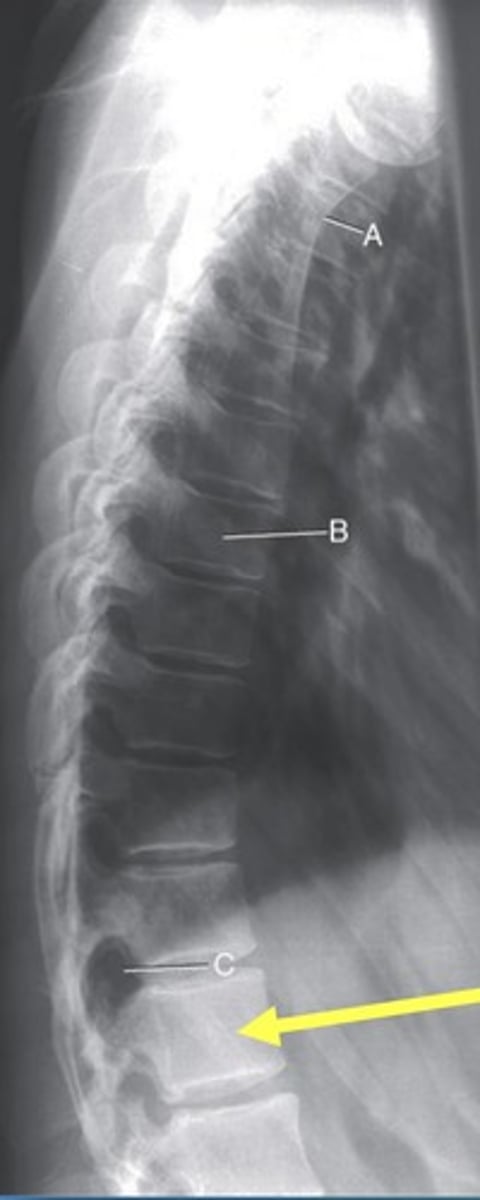

L2 Pedicle

A.

L2-3 intervertebral foramina

B.

L3-4 intervertebral joint space

C.

L4 body

D.

L5-S1 articular process

E.

Sacrum

F.

Greater sciatic notch

G.

L5-S1 joint

H.

Lateral Lumbar

What position?